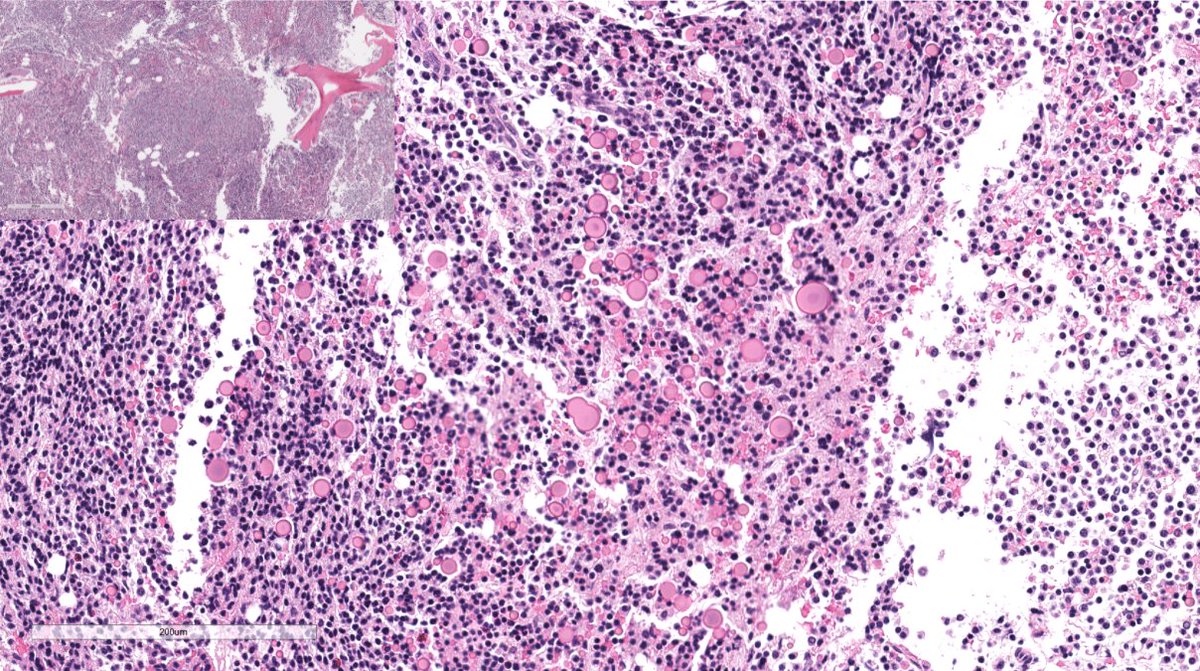

Disappearing glomeruli: loss of linear IgG in anti-GBM nephritis